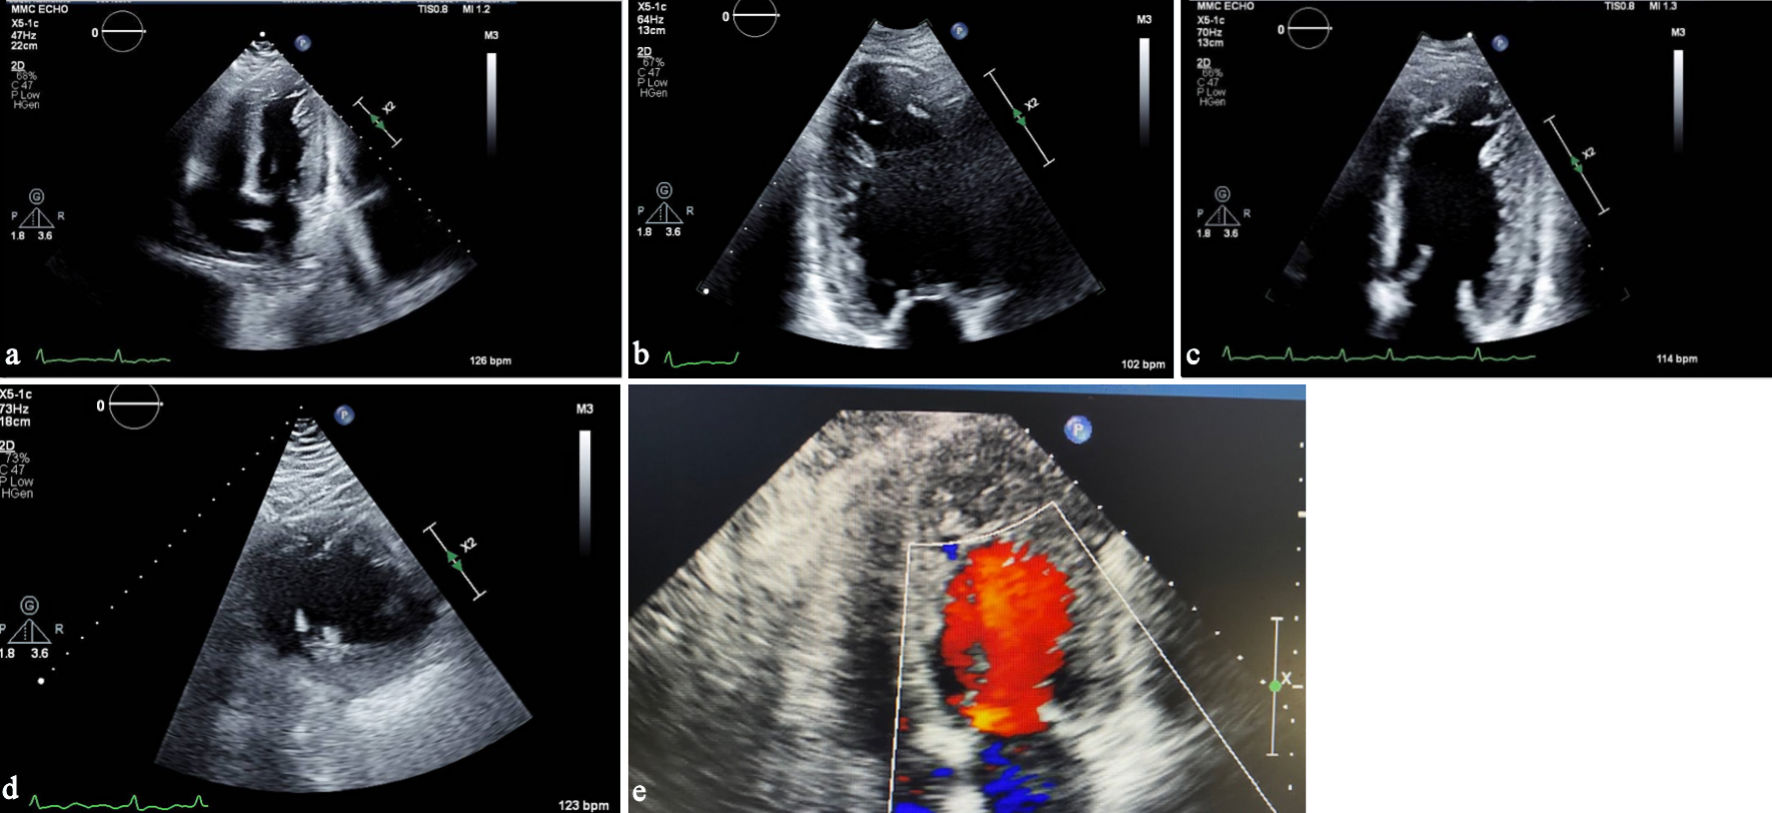

A 62-year-old non-smoking female with class II obesity, gastroesophageal reflux disease (GERD), diabetes mellitus complicated by stage 3A chronic kidney disease, and with no prior cardiovascular comorbidities, presented to the emergency room (ER) with dyspnea at rest. The patient had dyspnea on exertion for several months, which worsened acutely over the week prior to admission to the ER, and was associated with shortness of breath (SOB) upon lying down and swelling of both legs. She also reported an episode of chest tightness at rest 1 day before presenting to ER. Upon physical examination, she had an irregularly irregular rhythm, bilateral pitting pedal edema, basilar crackles, and a holosystolic murmur at apex. At presentation, her temperature was 36.9 °C, and her initial blood pressure (BP) was approximately 130–140/80–100. Her electrocardiogram showed AF with rapid ventricular response (Fig. 1) and inferior and anteroseptal Q waves. She was admitted for acute decompensated congestive heart failure (CHF). She had mild leukocytosis on presentation and throughout her hospital course (white blood cell (WBC) 11.9–17.7 × 103/µL). Chest X-ray revealed mild interstitial edema at the left base and excluded pneumonia. Transthoracic two-dimensional (2D) echocardiography showed a LVEF of approximately 25%, severe diffuse LV hypokinesis, normal right ventricular function, and a two-layered endocardium at apex and left lateral portion of the myocardium, suggestive of LVNC cardiomyopathy (Fig. 2).

Click for large image

Figure 2. (a) Transthoracic echocardiography, apical four-chamber view, demonstrating prominent trabeculations in the left ventricular apex. (b) Apical two-chamber view showing a two-layered myocardium with deep intertrabecular recesses. (c) Transthoracic echocardiography showing a left ventricular-focused apical four-chamber view illustrating a noncompacted-to-compacted myocardial ratio exceeding 2.0. (d) Parasternal short-axis view illustrating the noncompacted-to-compacted myocardial ratio exceeding 2.0 in systole. (e) Apical four-chamber view focused on the apex showing color-flow Doppler into recesses of apical trabeculations.

LVNC is typically identified through noninvasive imaging modalities, most commonly transthoracic echocardiography and CMR. Echocardiography serves as the initial diagnostic tool due to its broad availability. LVNC is diagnosed by marked trabeculations and a noncompacted-to-compacted myocardial ratio exceeding 2.0, although specific echocardiographic criteria and measurement conventions vary across studies, including the different views and whether measurements are taken at end-systole or end-diastole [7]. In our case, the noncompacted-to-compacted ratio clearly surpassed the diagnostic cutoff (Fig. 2). When standard imaging is limited by suboptimal acoustic windows, contrast echocardiography can enhance visualization of the endocardial borders and improve diagnostic reliability [7]. Notably, the diagnostic criteria employed for both echocardiography and CMR remain highly debated, reflecting variability in definitions, measurement techniques, and clinical thresholds.